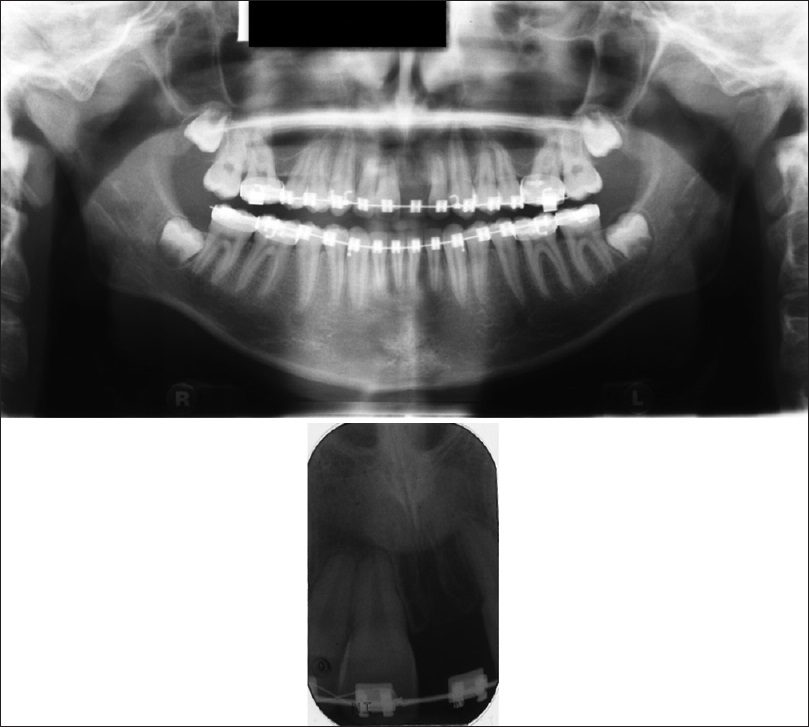

Figure 8. Finishing stage OPG and PA

Figure 8: Finishing stage OPG and PA